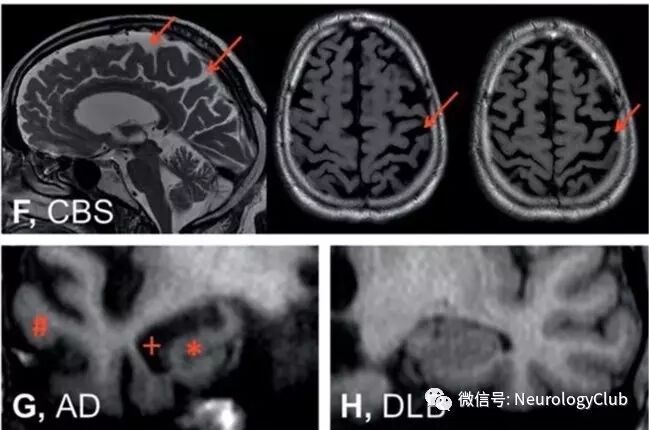

图2:在磁共振扫描中,脑干的正中矢状位提示帕金森氏病(PD)患者无明显特异性萎缩(图A),进行性核上性麻痹(PSP)患者可见中脑萎缩(*)(图B),多系统萎缩(MSA)患者可见脑桥萎缩(*)和小脑上蚓部萎缩(#)

图3:还有一些磁共振征象可以提示MSA,但并非高度敏感性的。T2WI序列脑桥可出现十字形高信号(脑桥十字征,*,图D),壳核可见低信号(*)伴边缘边缘高信号(壳核裂隙征,,图E

图4:在皮质基底节综合征(CBS)中(图F),不对称性的顶叶萎缩伴有脑回萎缩、脑沟加深(←)是其典型表现。如图G所示,海马萎缩(*)、颞叶萎缩(#)伴随着侧脑室颞角的扩张(+)是阿尔茨海默病(AD)患者的典型表现。但是这些表现通常不会在路易体痴呆(DLB)的患者中出现(图H)